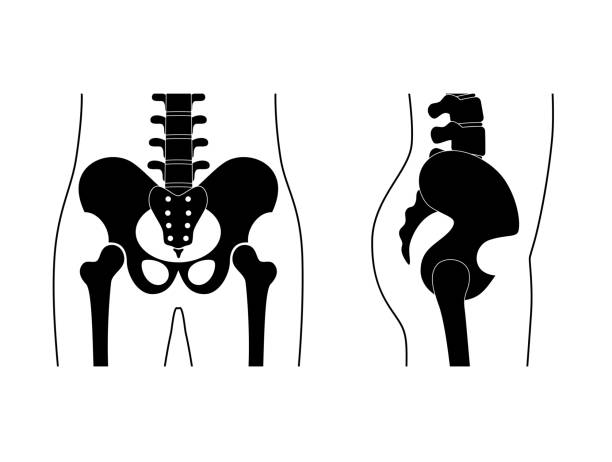

고관절 통증은 많은 사람들이 경험하는 문제 중 하나입니다. 이번 글에서는 고관절 통증의 주요 원인에 대해 알려드리겠습니다.

고관절 통증 원인을 제대로 파악하는게 중요합니다. 원인을 파악하면 어느정도 관리를 할 수 있기 때문입니다.

고관절 통증 원인-과도한 운동

과도한 운동은 고관절 통증의 일반적인 원인 중 하나입니다. 고관절은 운동 중에 큰 압력을 받고 자주 사용되는 부위이기 때문에, 지나치게 강도가 높거나 잘못된 자세로 운동을 할 경우 통증이 발생할 수 있습니다. 특히 고관절을 잘못 사용하여 부상을 입은 경우 통증이 지속될 수 있으며, 적절한 치료 없이 운동을 계속하게 될 경우 심각한 상태로 악화될 수 있습니다.

고관절 통증 원인-연령

고관절 통증은 연령에 따라 발생하는 경우가 많습니다. 고관절은 연령이 들수록 마모될 가능성이 높아지기 때문에, 노화로 인한 통증이 발생할 수 있습니다. 또한 연령에 따라 고관절 주변의 근육과 인대들이 약해질 수 있어 통증이 발생할 수도 있습니다. 따라서 노화에 따른 고관절 통증에 대한 적절한 예방과 관리가 필요합니다.

고관절 통증 원인-질환과 염증

고관절 통증은 다양한 질환과 염증으로 인해 발생할 수 있습니다. 관절염, 골관절염, 류마티스 관절염과 같은 질환은 고관절 통증을 유발하는 주요한 원인입니다. 또한 근육통, 건염, 인대염과 같은 염증도 고관절 통증을 초래할 수 있습니다. 이러한 질환과 염증은 적절한 치료와 관리가 필요하며, 통증이 계속되는 경우 전문의의 진단과 치료를 받아야 합니다.

고관절 통증 원인-부상

고관절 통증은 부상에 의해 발생할 수도 있습니다. 스포츠나 사고로 인한 고관절 관련 부상은 통증과 함께 발생할 수 있으며, 시간이 지남에 따라 통증이 지속될 수 있습니다. 부상을 받게 되면 신속하고 적절한 치료를 받아야하며, 전문적인 재활치료를 통해 고관절을 회복시켜야 합니다.

고관절 통증은 일상 생활에 큰 영향을 미치는 문제입니다. 적절한 예방과 치료를 통해 고관절 통증을 줄이고 관리하는 것이 중요합니다. 만약 고관절 통증으로 고민이라면, 전문적인 의료진과 상담하여 적절한 치료방법을 찾는 것을 권장합니다.